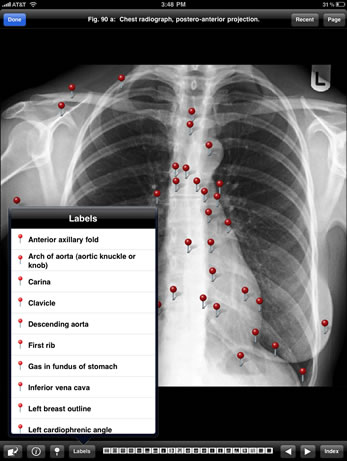

Preview the Imaging Atlas of Human Anatomy, featuring select images of the healthy human body as seen through a wide range of modern imaging techniques.

This Sampler is based on the print atlas, the Imaging Atlas of Human Anatomy, 4th Edition, written by Jamie Weir, Peter Abrahams, Jonathan D. Spratt, and Lonie Salkowski. The complete Atlas, also available in the modalityBODY Store, offers a comprehensive view of the structures and relationships within the body through a variety of imaging modalities.